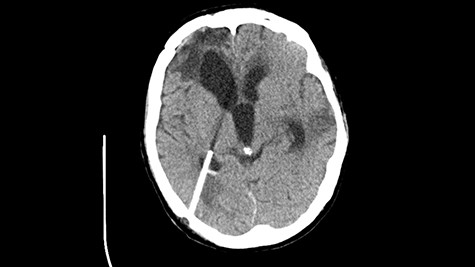

Head CT after polypectomy—seen sphenoid sinus and both maxillary sinuses filled with blood. (Department of Neurosurgery own material).

In described case, a head CT scan after polypectomy confirmed the subarachnoid hemorrhage (Fig. 1). In addition, the presence of air in the ventricular system was visible, and presence of defects of the upper left orbital wall and ethmoid on both sides (Fig. 3). In the CT scan sphenoid sinus, frontal and ethmoidal sinuses on both sides and right maxillary sinus airless, filled with blood and soft tissue. The changes also concerned the lateral part of the left maxillary sinus (Fig. 4).